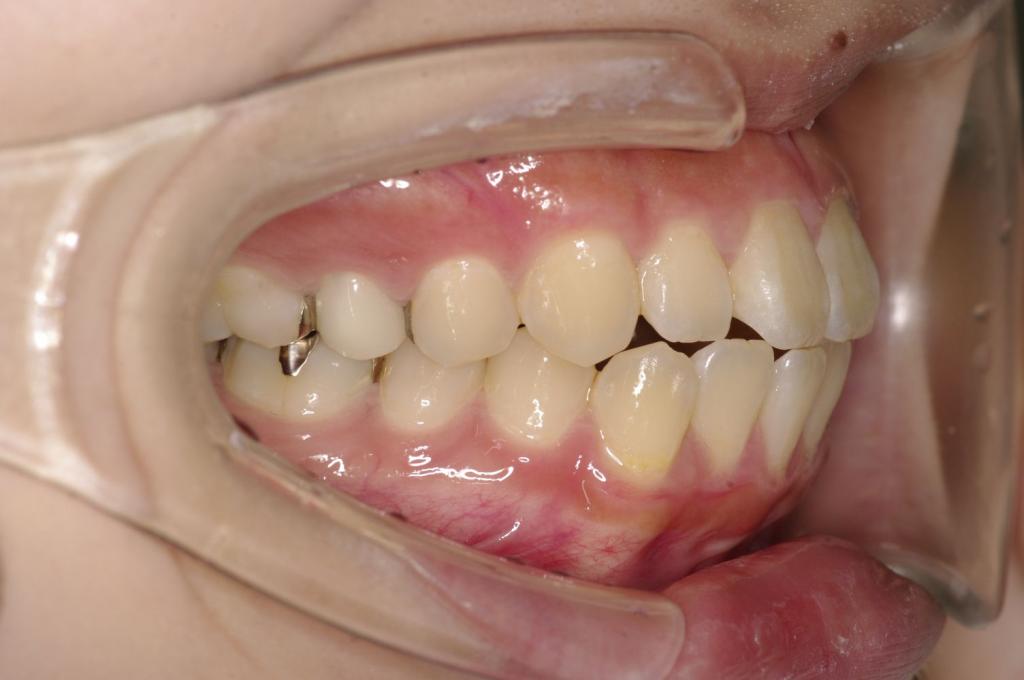

顎、顔の歪みの矯正治療

(治療期間、治療前後写真、治療方法、費用)WORKS